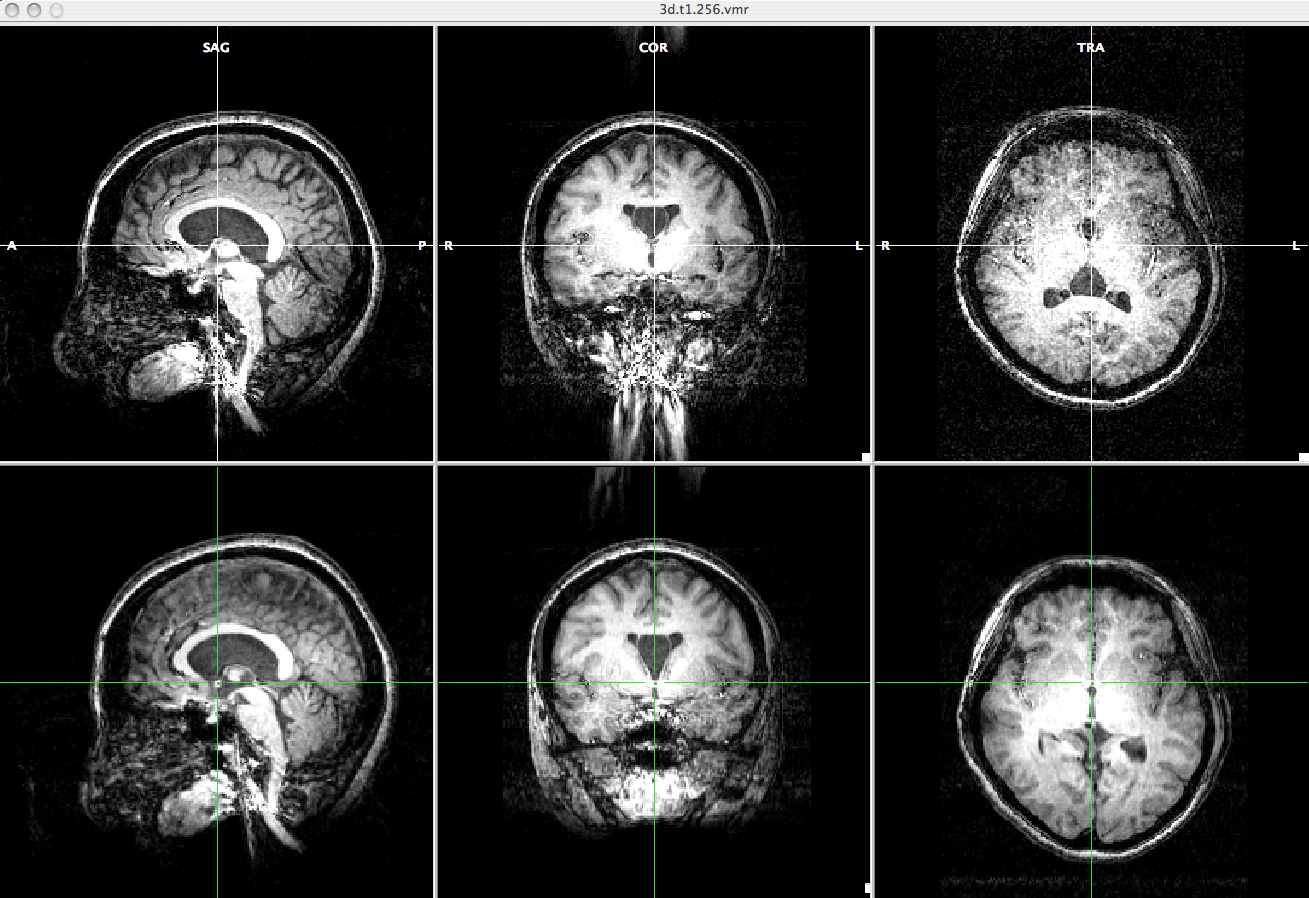

In this process, we will make the low resolution anatomical image to have the same view as the high resolution anatomical image for later alignment.

- Open anat.low.vmr file.

- Select "Spatial Transf" and click "To Sag" if the SAG view of the anat.low.vmr dataset does not show sagittal plane.

- Click "Iso-Voxel" and you will see "Iso-Voxel Transformation" dialogue. Check the Source voxel size is correct and press "OK".

-> You will get anat.low_SAG_ISO.vmr file.

- Open anat.high.vmr file

- In the "3D Volume Tools" dialogue, choose "Coregistration" and click "Select VMR..." button to select anat.low_SAG_ISO.vmr file for VMR-VMR coregistration.

Press "Align..." then "GO" in the "VMR-VMR Coregistration Options" dialogue. - Select "Spatial Transf" and click "Save .TRF" to save the parameter file for this spatial transformation.

-> You will get the anat.high_Man.trf file.